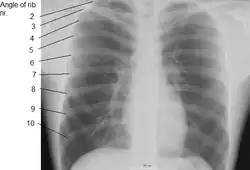

Imágenes adicionales

-

Superficie anterior del esternón y cartílagos costales. -

Imagen de rayos X del tórax humano, con las costillas marcadas. -

Simulación 3D de la caja torácica -

Proyecciones superficiales del tronco, incluyendo cada costilla, y el margen costal.